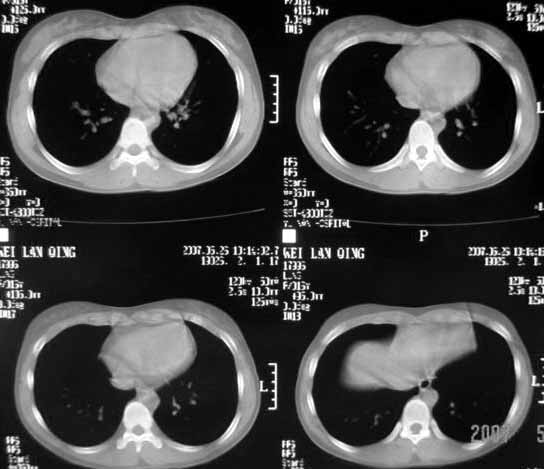

以下是引用dyqct在2007-5-26 12:01:00的发言:[br]右第二肋腋侧呈明显膨胀性、分叶状改变,内无明显间隔,ct值49hu,病变大小约67x57mm,周围硬化缘无断裂,内缘见多数骨嵴,肿块与正常骨间界限清楚。无移行带。周围软组织无浸蚀,胸膜腔无积液。[br]考虑:1、右第二肋动脉瘤样骨囊肿可能性大;[br] 2、需同骨巨细胞瘤、浆细胞瘤、骨纤鉴别。